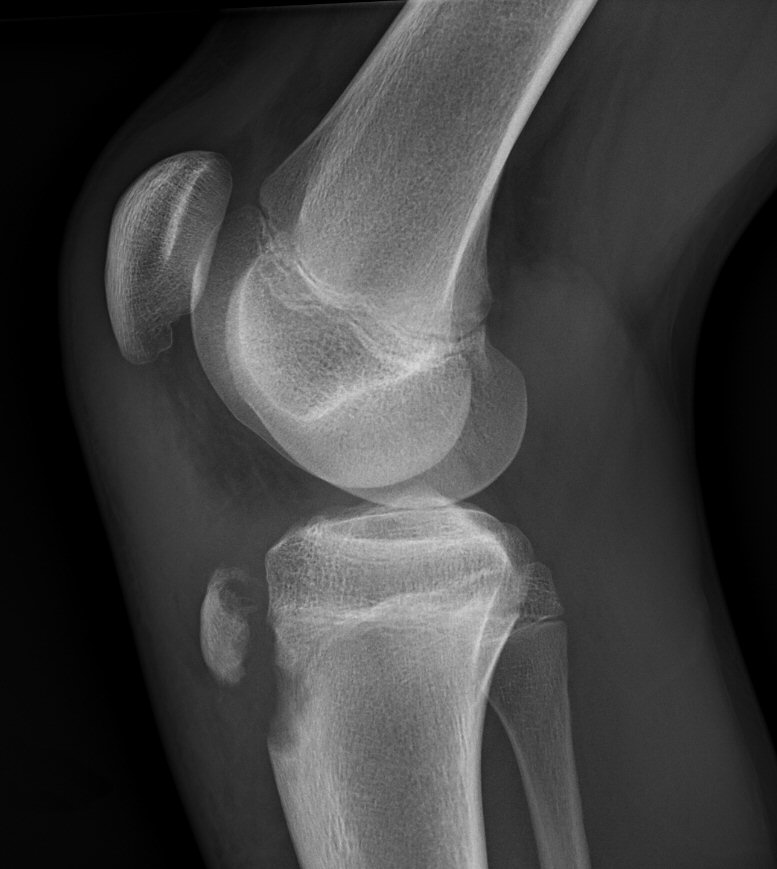

Avulsion av processus tibiae, fixerad med två skruvar.